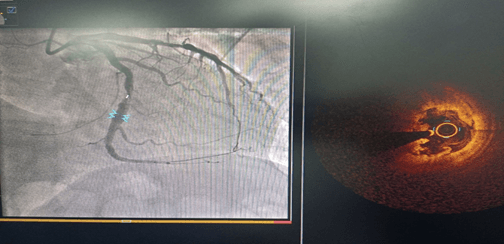

术前CAG示:LCX中段80%狭窄 ;OCT示纤维斑块,最小管腔面积3.1mm2

术后OCT示:支架贴壁及膨胀良好,无夹层及血肿